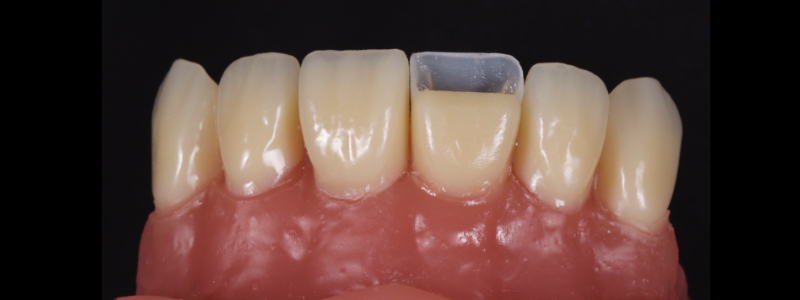

To achieve this, the achromatic enamel mass is first placed on a PVS Putty stent made from a diagnostic wax-up with a flat plastic (see the first article in this series for more detail). The enamel mass is thinned with a flat plastic in combination with a multipurpose condenser, a #3 brush (i.e., GC, Cosmedent, Tokuyama), and some modeling resin (Fig. 7).

A modeling resin is a liquid resin that does not contain HEMA — examples include modeling resin (Bisco), Brush and Sculpt (Cosmedent), and Signum (Kulzer). The unpolymerized resin is then carried in the stent to the tooth and adapted to the palatal margin with a #3 brush (Fig. 8).

Before polymerization, the contact points are cleared with an Interproximal Carver Long (IPCL) like American Eagle (Fig. 9). The resin mass is then polymerized to create a palatal shell (Fig. 10).